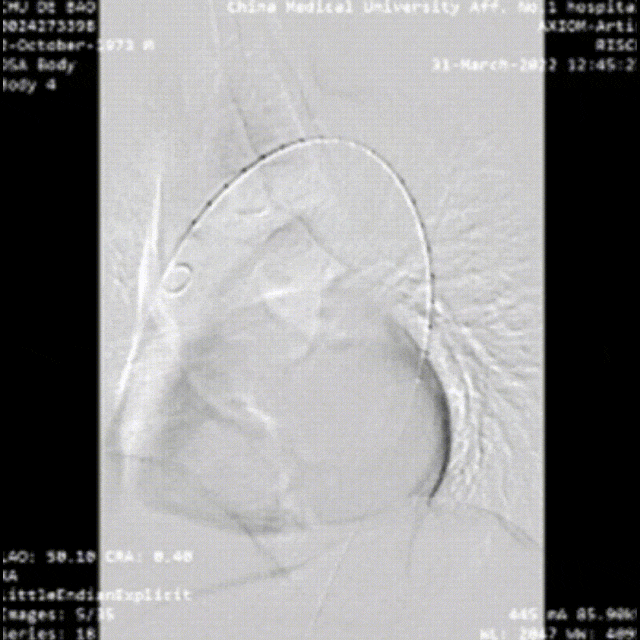

28岁男性,急性复杂型B型AD,急诊TEVAR治疗

48岁男性,胸腹痛20小时,右下肢一过性麻木,TEVAR治疗